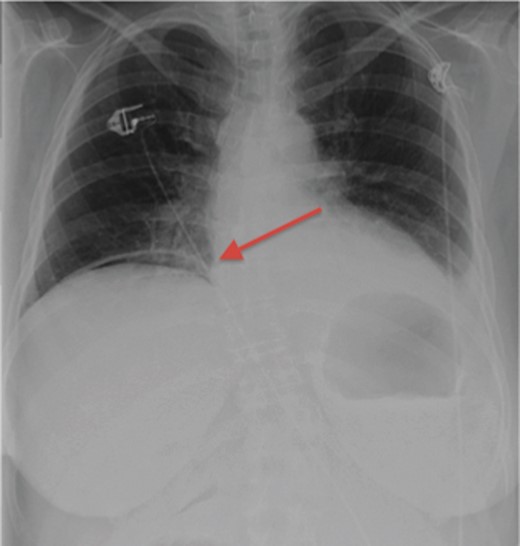

Her initial labs showed a normal WBC level of 8.3 thou/mcL; however, the patient was acidotic with a pH of 7.29 and a lactic acid level of 3.5 mmol/l. An acute abdominal series was obtained demonstrating free air below the right hemidiaphragm (Fig. 1). Physical examination showed a distended abdomen with tenderness, guarding and signs of peritonitis. The patient was subsequently boarded for an exploratory laparotomy with repair of perforated viscus, as that is the usual cause of pneumoperitoneum, especially under the right hemidiaphragm. Because the patient's vital signs stabilized after being resuscitated, the decision was made to obtain a CT scan to better assess the location of the perforated viscus. Much to our surprise, the patient did not have a perforated viscus, but a splenic abscess that had ruptured causing the pneumoperitoneum (Fig. 2).

CT scan demonstrating gas-forming splenic abscess and free air in the peritoneal cavity.